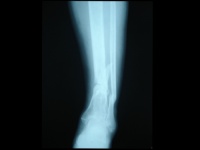

在临床上,一旦怀疑有胫腓骨骨折,就要拍摄小腿正侧位的X线片,照片质量要求较高,除了能发现明显骨折外,对怀疑的线状裂纹也要确定,因为线状骨折也影响愈后和治疗,如行内固定,其稳定性要把线状骨折的因素考虑在内。

在晚期估计其愈合的程度时,有时要拍摄透过骨折端的斜位片。复位后的x线片最好包括膝、踝两个关节,以确定这两个关节轴线在平行的位置,防止晚期因膝、踝关节面的不平行而造成的并发症。原则上拍小腿x线片时要包括胫腓骨的全长。以防止低位胫骨骨折,合并有高位的腓骨骨折发生漏诊。

在骨的x线描述上,首先确定骨折的部位,在上l/3、中l/3或下1/3。再确定骨折类型是横断、斜行或螺旋型骨折,骨折有无粉碎,以及是否多段。侧方移位严重则愈合很难。×线片上不易确定上下骨折段的旋转移位,要从临床上来判断和纠正。